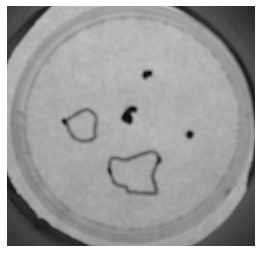

Low magnification picture from a Petri dish in which 5 explants are initially placed. 3 weeks after, 3 explants, marked with a dot, were not able to produce an efficient innervation and the 2 latter explants innervated large muscle areas which were delimited by a line.